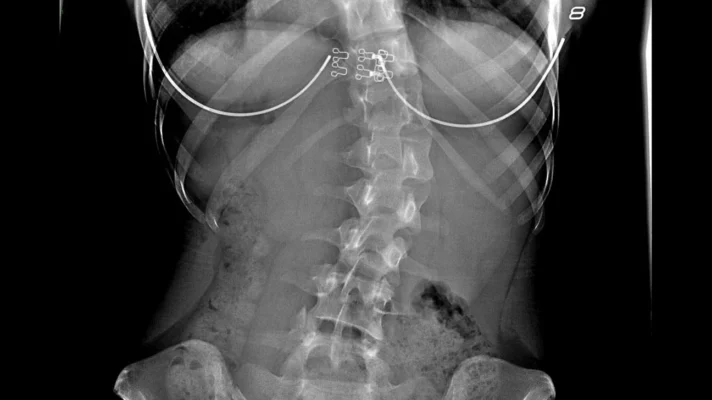

Tethering-Skoliose: Innovative nicht-fusionierende Techniken für eine wirksame Skoliosekorrektur

Discover innovative non-fusion techniques for effective scoliosis correction with tethering. Explore advanced solutions for spinal [...]